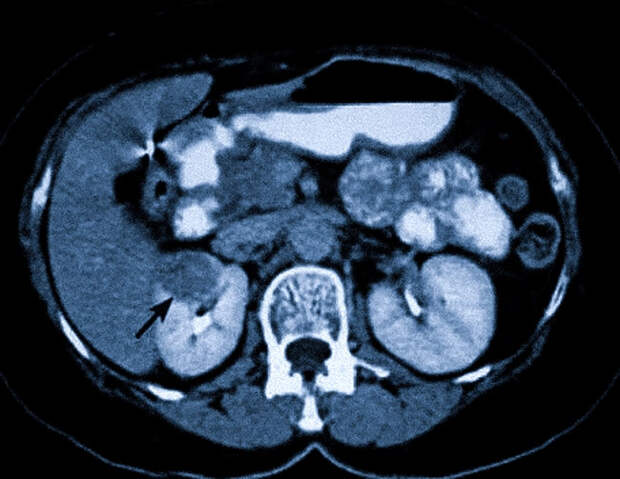

Показаниями к проведению исследования являются подозрения на наличие опухолей, воспалительных процессов или патологических изменений почек, надпочечников, поджелудочной железы, а также сосудов и лимфатических узлов забрюшинного пространства.